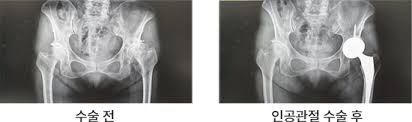

고관절 수술은 다양한 이유로 시행될 수 있지만, 일반적으로는 고관절 관절염, 외상, 또는 선천적인 기형 등으로 인해 통증이나 기능 저하가 나타날 때 이루어집니다. 이 수술에는 인공관절 치환술, 관절경 수술 등의 방법이 있으며, 각각의 수술 방법은 회복 단계와 필요한 시간에 서로 영향을 미칩니다. 고관절 수술의 주된 목적은 통증을 감소시키고, 이동성과 일상생활의 질을 향상시키는 것입니다. 그러므로, 환자는 수술 후 생활 습관을 조절하고, 적극적인 rehabilitative 간호를 통해 빠른 회복을 도모해야 합니다.

- 인공관절 치환술: 가장 일반적인 고관절 수술입니다. 퇴행성 관절염이나 심한 외상으로 인해 고관절이 손상된 경우, 인공 관절로 대체합니다. 이 수술은 대개 1-2시간 가량 소요되며, 회복이 길어질 수 있습니다.

- 진단적 검사: 의사가 필요할 경우 정기적으로 X-ray나 MRI를 통해 관절의 상태를 체크할 수 있습니다.